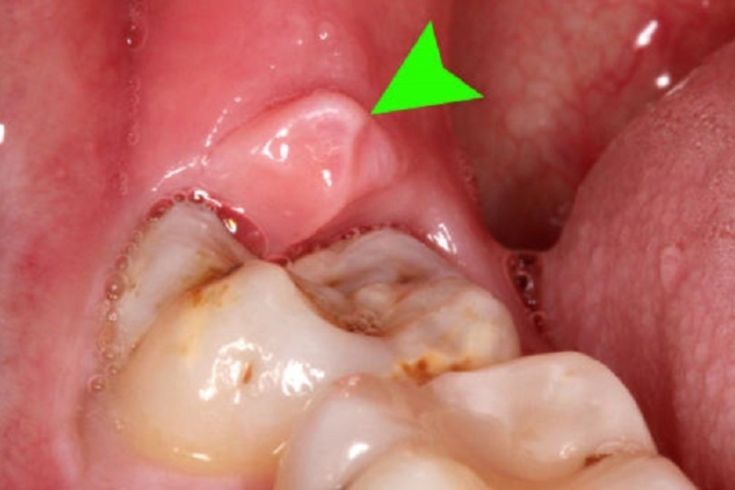

Loét và hoại tử: Vết loét hoại tử hình thành tại các nhú nướu, có vết lõm rõ ràng và thường phủ bởi lớp giả mạc màu trắng. Việc lấy lớp giả mạc ra sẽ làm lộ mô nướu dễ bị chảy máu và rất đau.

Viêm nướu hoại tử cấp tính (Acute Necrotizing Ulcerative Gingivitis – ANUG) là một dạng nhiễm trùng nướu nghiêm trọng, đặc trưng bởi tình trạng hoại tử mô nướu, gây đau đớn và chảy máu.

- Xuất hiện lớp giả mạc màu xám trên nướu